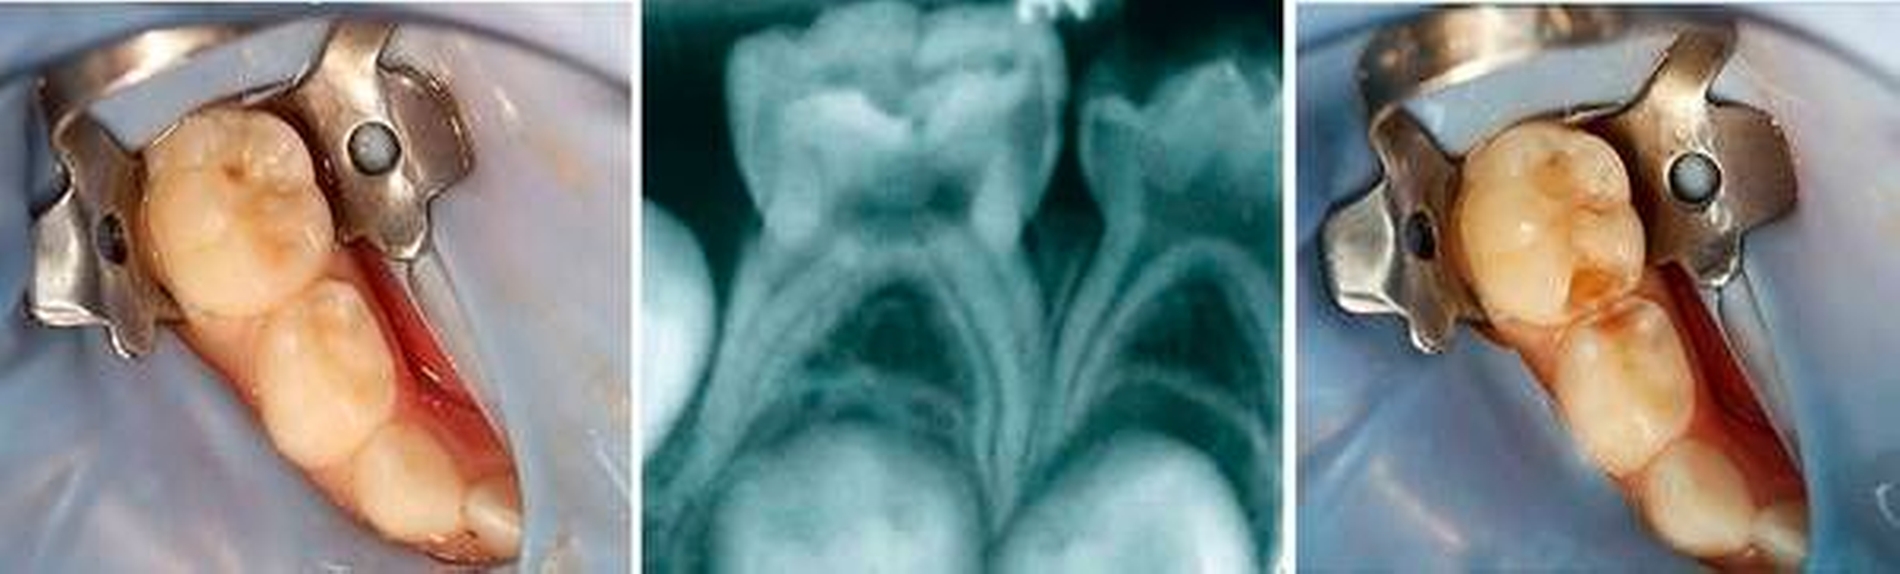

Zentraler Anspruch der Kinderzahnheilkunde ist: Jeder Milchzahn sollte (wenn überhaupt) nur einmal behandelt werden. Daher sind frühzeitige sowie regelmäßige zahnärztliche Kontrollen unerlässlich. Neben einer soliden klinischen Untersuchung (Karies, Zahnfarbe, Schwellung, Rötung, Fistel, Zahnbeweglichkeit in Abhängigkeit von Zahnwechsel, Zustand der Nachbarzähne) spielt die röntgenologische Diagnostik (Umfang der Karies, interradikuläre Aufhellungen, Resorptionen, Lage des Zahnkeims) für die vorausschauende Planung und für die erfolgreiche Therapie eine wichtige Rolle. Vor allem die Röntgenuntersuchung bringt meistens einen entscheidenden Mehrwert, da die Karies bei Kindern aufgrund der breiten, flächigen Approximalkontakte klinisch oft sehr schwer zu diagnostizieren ist (Abbildung 1) [Fuks, 2005].

Auch wenn Eltern sich besorgt in Hinsicht auf die Röntgenstrahlung zeigen, sollte keine Therapie ohne Röntgenbild stattfinden. Nicht selten endet eine scheinbare Fissurenkaries in einer Caries profunda, die mit einer Krone versorgt werden muss. Um sowohl Sicherheit für die Therapieentscheidung zu erlangen als auch die Eltern rechtzeitig über die Intervention aufzuklären, ist das systematische Röntgen bei Kariesverdacht unerlässlich. Bei einer noch nicht kavitierten Läsion am Einzelzahn sollten auch die Zähne des antagonistischen Kiefers mithilfe von Bissflügeln untersucht werden (Abbildung 2).

Wenn bereits Schmerzen oder eine umfangreiche Zerstörung an einem Zahn vorliegen, muss ein Zahnfilm angefertigt werden, um das mittlere Wurzeldrittel beziehungsweise die interradikuläre Zone beurteilen zu können. Der dünne Pulpaboden besitzt viele akzessorische Kanäle, so dass sich eine Pulpitis nicht wie bei einem bleibenden Zahn periapikal, sondern meistens interradikulär im Sinne einer Osteolyse im Bereich der Bi- oder Trifurkation darstellt [Waterhouse et al., 2011; Van Waes und Steffen, 2009].

Röntgenologisch zeigt sich die umgebende Knochenstruktur des Zahnes unauffällig ohne interradikuläre Aufhellungen beziehungsweise Resorptionen. Die Wurzel sollte mindestens zu zwei Dritteln vorhanden sein (Abbildung 6). Die Erfolgsaussichten der Vitalamputation hängen somit von der korrekten klinischen und radiologischen Pulpadiagnostik ab [Seale und Coll, 2010].